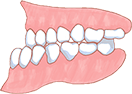

こんな症状ありませんか?

デコボコ

出っ歯

すきっ歯

受け口

開咬

この様な習慣が続くと、上アゴの発達が悪くなり下アゴの発育の大きな影響が出てきます。アゴがうまく成長できない結果、歯並びはどんどん悪化していきます。

成長期のお子さんの口呼吸がお子さんの上顎骨の発育に影響を与えます。上顎骨は上の歯の根っこを支えるだけでなく上唇付近から目の下までの中顔面を作っています。つまり歯並びだけでなくお顔付きにも影響をあたえます。